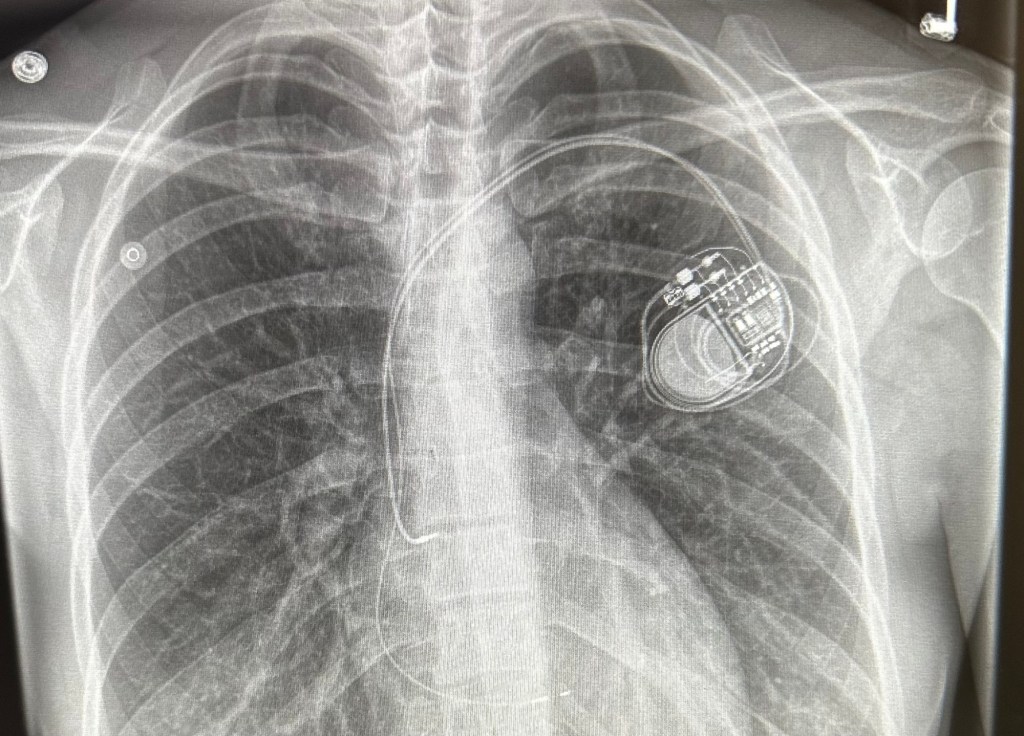

January 3rd, 2024 I underwent surgery and received a pacemaker, which I will rely on for the rest of my life. We still don’t have clear answers as to why this happened or what caused it and we may never get those answers. What I do know is God showed up so many times and in ways I’ve never experienced before. It was so evident that he was and is the defender of my heart and he spared my life… he knew I had more work to do down here on earth!